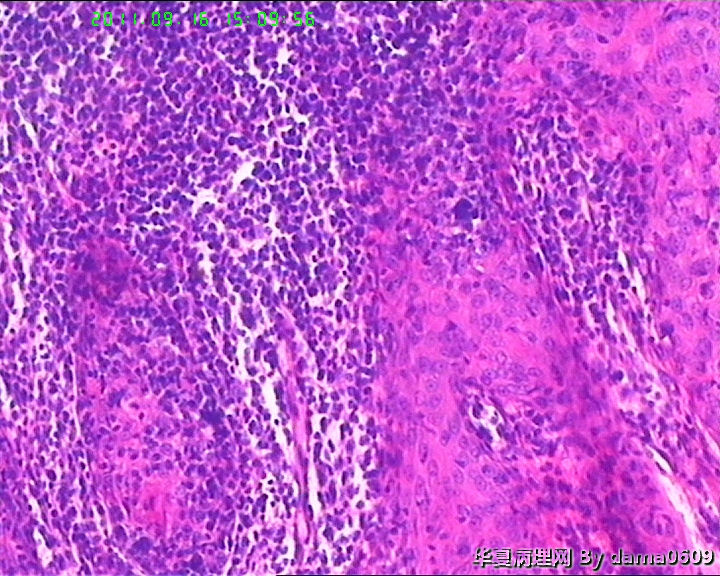

• 背部肿物,急请老师看看!!图2

图2

考虑T细胞淋巴瘤:依据1.淋巴样细胞浸润破坏性生长达肌组织;2.淋巴样细胞异型:核形不规则,大小不一,胞浆较丰富.注:表面上皮有增生需排除炎性反应.